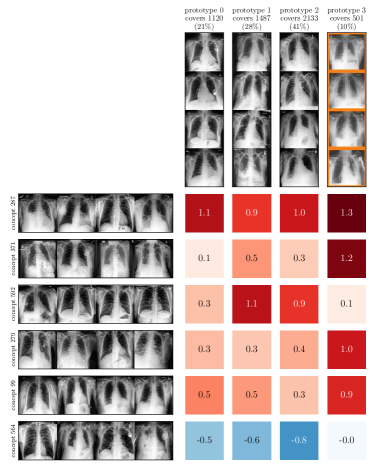

For example, Prototypical Concept-based eXplanations (PCX) [27] train Gaussian Mixture Models on max-pooled latent relevance scores and consider cluster means as stereotypical explanation, encoded as distribution over concepts (i.e., neurons).

Both input and latent relevance clustering require subsequent human supervision to determine whether outlier clusters represent valid or spurious behavior. To semi-automate this process, Anders et al. [3] propose using Fisher Discriminant Analysis [37] to rank class-wise clusterings by linear separability, while Dreyer et al. [27] computes similarities between prototypes. The results of clustering approaches can serve as an initial set for bias modeling methods outlined in Sec. 3.2, which can be refined iteratively. An example outlier cluster of latent relevances is shown in Fig. 4 (top), with all samples containing the spurious band-aid concept.

6.2 Concept Validation: Identification of Spurious Behavior

Given the fitted models, we apply bias identification methods introduced in Sec. 4 to detect the expected spurious model behavior. Throughout this section, we focus on the ResNet50 model trained on ISIC2019 with various confounders. We further limit our analyses to samples from the melanoma class to prevent that clustering model behavior results in clusters representing different classes, and instead allowing us to identify spurious sub-strategies for predicting the considered class.

Data Perspective

We first apply SpRAy in input and latent space, computing input feature importance scores using LRP summed over color channels. To obtain latent relevances, we use intermediate relevance scores in the LRP computation process after the (out of four) residual block, max-pooling over spatial dimensions to yield relevance scores for layer with channels. The clustering of pairwise cosine distances between heatmaps is shown in Fig. 6 (top left). Detected outlier clusters contain samples with spatially coherent biases, e.g., the black circle around the lesions originating from microscopes (). In contrast, clustering latent relevance scores reveals more complex, less spatially dependent clusters, as shown in Fig. 6 (top right), including the ruler artifact () and the microscope (). Compared to those in input space, the cluster for the microscope in latent space represents a more diverse high-level concept. In the input space visualization, we further highlight samples from the ruler cluster detected in latent space. Instead of forming a cluster, they spread across the entire embedding space, indicating that the bias is too complex to be detected in input space.

Model Perspective

Next, we apply bias identification approaches from the model perspective by identifying outlier neurons based on activation pattern via DORA and relevance pattern by clustering pair-wise cosine distances between concept relevance scores. We focus on latent activations and relevances after the third residual block. DORA uses a distance function based on how neurons activate upon each others n-AMS, achieving high similarity when neurons activate upon similar input signal. A 2D visualization of the resulting distance matrix is shown in Fig. 6 (bottom left). Identified outlier concepts include ruler () and (white) hair (). We further compute pairwise cosine distances between latent relevance scores , aggregated over spatial dimensions, and apply UMAP to embed the resulting distance matrix in . This results in high similarity between neurons (concepts) that the model uses similarly for predictions. The concept clustering is visualized in Fig. 6 (bottom right), highlighting two outlier clusters focused on rulers () and blueish tint ().

Results for other classes, model architectures, and datasets are presented in Appendix A.6.1. This includes experiments with ECG data in Fig. 10, revealing the artificially inserted static noise in the attacked lead from both data and model perspectives. Notably, dominant spurious concepts, such as the artificial timestamp in HyperKvasir or the static noise in PTB-XL, may not be detected as outlier concepts. In such cases, analyzing prediction sub-strategies via PCX may provide additional insights on spurious inlier behavior. Hard-to-interpret concept representations pose another challenge for the model perspective. For example, the brightness artifact in CheXpert is not clearly visible in the concept UMAP (see. Fig. 15, right), but can easily be detected using SpRAy (Fig. 15, left) or PCX (Fig. 22). In summary, while all considered spurious features are detected, the choice of bias identification approach is crucial, as some shortcuts are easier to detect as outlier concept (e.g., ruler) and others via PCX (e.g., brightness, static noise in ECG).